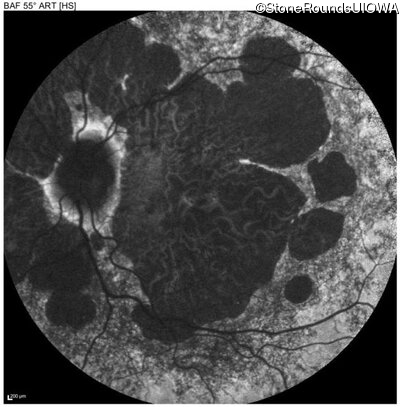

Age at visit: 54 years

Age at visit: 54 years (Visit 2)